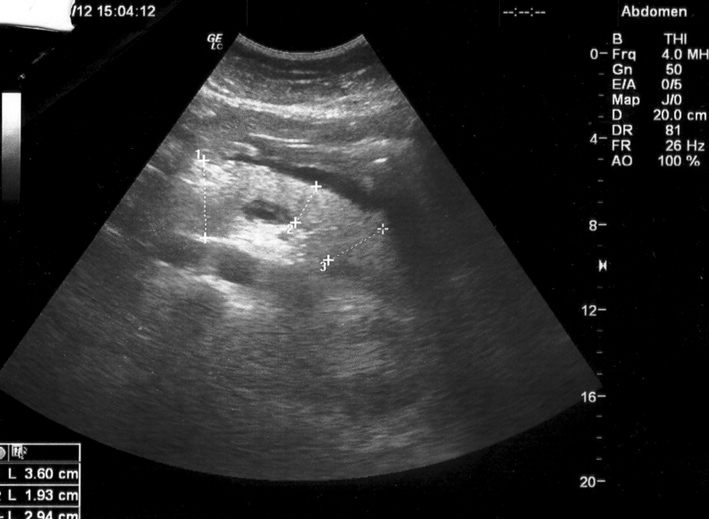

Молодой парень, днем стал сильно болеть живот, поздним вечером поступил в БСМП.

Logiq C5

на первой эхограмме увеличение головки панкреас, оментобурсит...

На сонограммах о.панкреатит, в первый и следующий день после начала заболевания. Обратите внимание на изменение эхогенности железы и на два признака, которые позволили диагностировать заболевание в первый же день.

Самое интересное что эхогенность железы нормальная, даже несколько повышена, а вот размеры и парапанкреатический инфильтрат за о.панкреатит.

жидкость в полости малого сальника + компрессия сел. вены!

Да, видим выпот кпереди от панкреас (действительно, в сальниковой сумке) и выпот между телом панкреас и селезеночной веной.

Причем второй признак - по моим наблюдениям - является самым ранним и быстро исчезает.